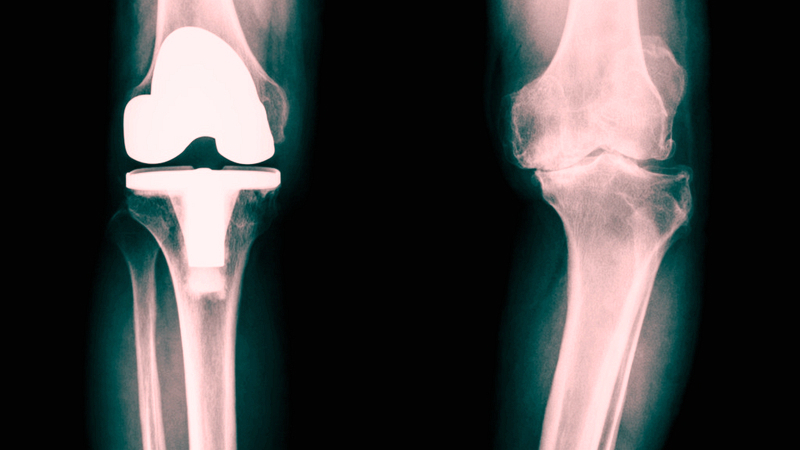

为什么会得关节炎?这和不同的关节炎的不同发病机制有关。关节炎按照病理生理学分类,可以分为两大类:(1)非炎症性关节炎:退化性关节炎和创伤性关节炎a) 退化性关节炎:通常情况下,是最常见的关节炎,也是我们口中常说的“关节炎”,大部分是老人家得,起因是关节软骨的退化,也就是关节磨损了,老化了,因此也叫“老年性关节炎”。b) 创伤性关节炎:因为关节受过外伤,导致关节内结构损伤,迁延不愈,逐渐加重,形成关节炎性改变,跟年龄关系不大,老人和年轻人都会得。